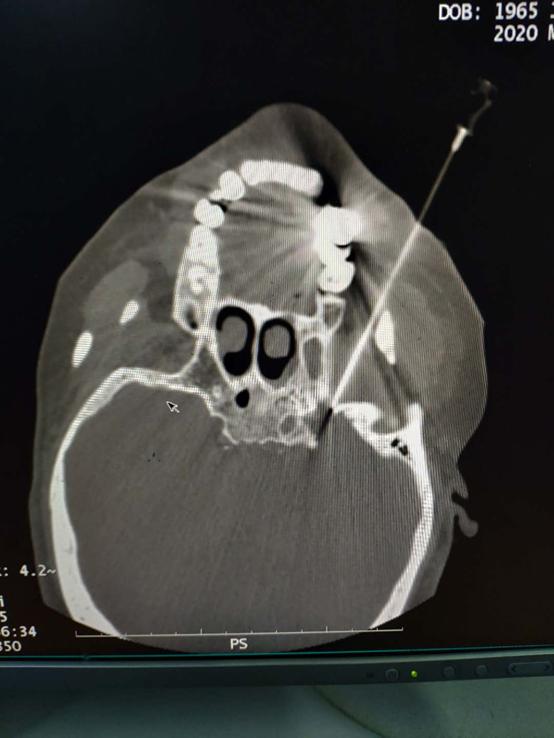

4.CT引导下三叉神经射频消融术